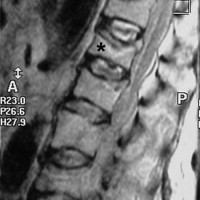

A free medical education seminar series for everyoneA FREE spine education seminar series for everyone Back pain has many faces and to many people it can be distressing, disabling or even frightening. Whether back pain comes from a strain, degenerative disc disease, a herniated disc, spinal stenosis, spondylolisthesis, a complex deformity or even a fracture, there are many options that can help you to live an active lifestyle. Additionally, osteoporosis is another disease that you may not even know you have. Learn from these dynamic experts about the various types of back problems and the latest treatments available. We will discuss the problems, the solutions and leave time for your questions to help you be active. Talk with the experts and get your concerns addressed. Spine Program